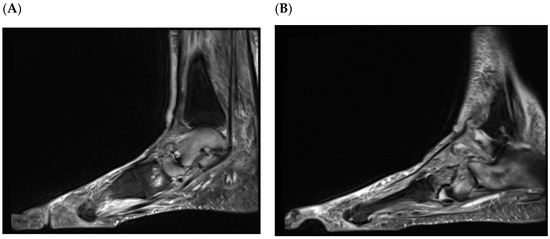

Burning Issues/Hot Topics: The Charcot Foot

by Victoria E. L. Milbourn, Ava Khoshnaghsh, Michael E. Edmonds and Nina L. Petrova

J. Clin. Med. 2026, 15(5), 1993; https://doi.org/10.3390/jcm15051993 - 5 Mar 2026

Charcot neuro-osteoarthropathy remains one of the most serious complications of diabetic neuropathy, with the potential for rapid progression to deformity, ulceration and limb-threatening outcomes. The earliest signs and symptoms are often subtle and easily missed, yet early recognition provides a narrow window of [...] Read more.

Charcot neuro-osteoarthropathy remains one of the most serious complications of diabetic neuropathy, with the potential for rapid progression to deformity, ulceration and limb-threatening outcomes. The earliest signs and symptoms are often subtle and easily missed, yet early recognition provides a narrow window of opportunity to prevent irreversible structural change. Contemporary diagnostic pathways are underpinned by close clinical observation and correlation of bedside findings with detailed imaging analysis, enabling earlier identification of active disease before collapse occurs. This article provides a comprehensive overview of the Charcot foot, integrating clinical presentation, differential diagnosis and current approaches to investigation and management. It also highlights the challenges of monitoring disease activity over time, including remission and relapse, and the importance of timely specialist referral and multidisciplinary management. By reinforcing structured assessment and targeted intervention, this review aims to support consistent, evidence-informed care for people affected by Charcot neuro-osteoarthropathy. Full article

(This article belongs to the Special Issue Diabetic Foot: Emerging Prevention Strategies and Epidemiology)

Show Figures

Figure 1